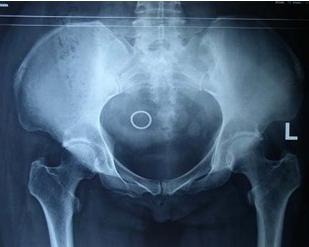

众所周知,骶髂关节炎在生活中属于一种比较严重的疾病,尤其是它发病时所伴随的剧烈疼痛更是给患者的身心健康造成了严重的折磨,因此很多人都想知道,强直性脊柱炎为何以侵犯骶髂关节为主?下面请成都风湿病医院医生来对骶髂关节炎的病因做一个详尽的回答。

首先其中一个原因就是骶髂关节容易受到外伤和压力的侵扰,而且是连接众多组织的关键位置,与解剖位置有关骶髂关节是由骶骨与髂骨的耳状关节面相互连接而成的微动关节,活动度小,是重力传导的必经要道,而组成骶髂关节的关节面在成年后高低不平,呈犬牙交错状,关节囊紧贴关节面,尽管有坚强韧带使关节牢固连接,但由于骶髂关节构造方面的特点,易遭受重力及外力的损伤。

其次是与骶髂关节的结构有关,容易引起炎症,感染途径较多,也成为强直性脊柱炎影响较大的原因之一,与组织结构特点有关骶髂关节周围的韧带较密集,它毗邻直肠、膀胱及子宫(女性)、前列腺(男性)等毛细血管丰富的器官,前三者都是与外界相通的空腔器官,增加了外界细菌感染的途径。

与感染有关骶髂关节的解剖位置及组织结构决定了其感染机会增高,骶髂关节附近有丰富的血液及淋巴循环,一方面供应营养,但另一方面也为细菌滋生及繁殖创造了良好条件。相关推荐:为何强直性脊柱炎易导致骶髂关节炎